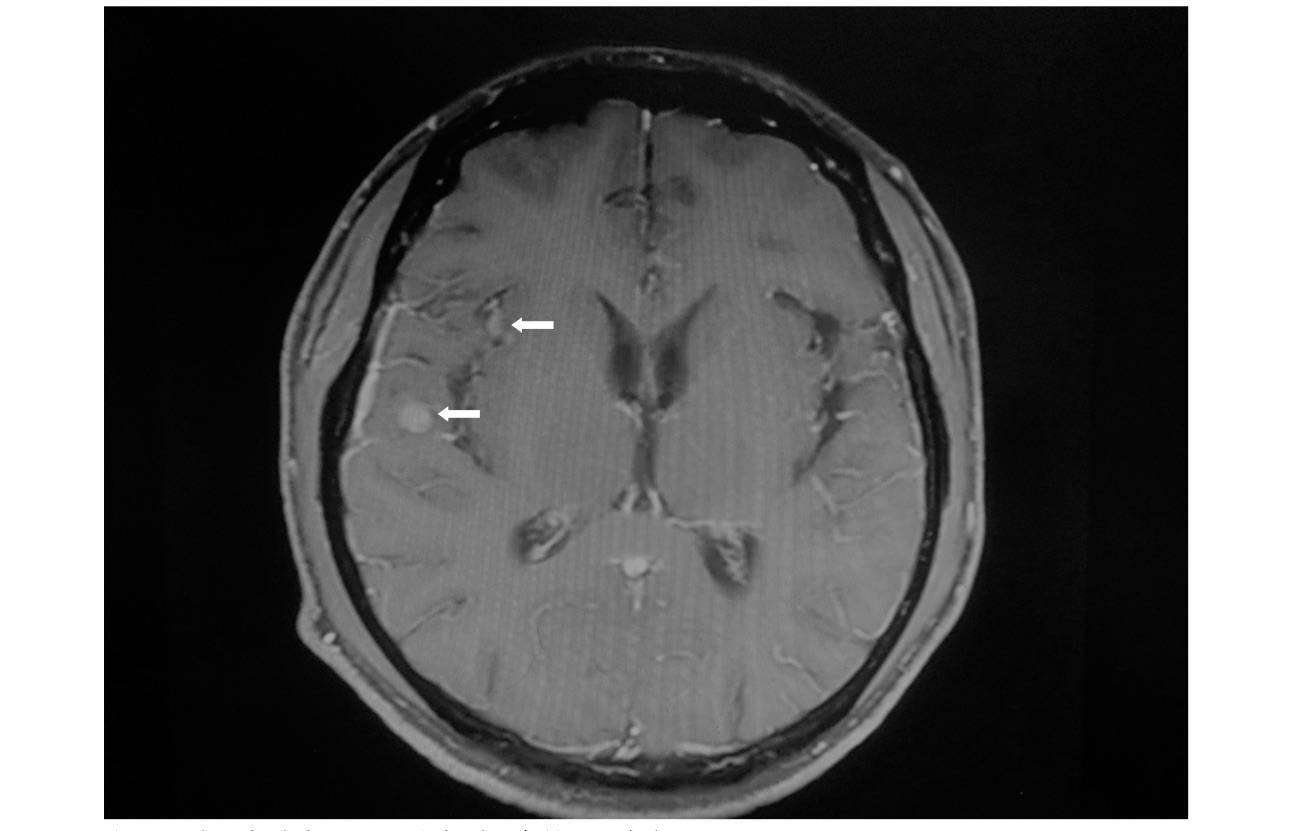

颅脑转移瘤mri特点(网络远程会诊病例)

图片尺寸600x377